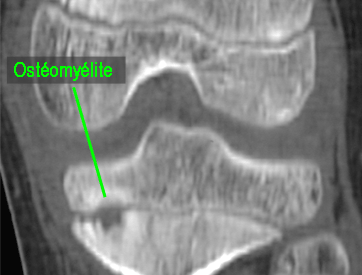

Pathologies infectieuses osseuses

Il s'agit des ostéomyélites sub-aigues et chroniques.

Ce sont des infections

bactériennes des os qui se développent doucement, sans

provoquer des signes généraux (ni fièvre, ni frisson,

ni altération de l'état général) et qui

s'accompagnent de douleurs.